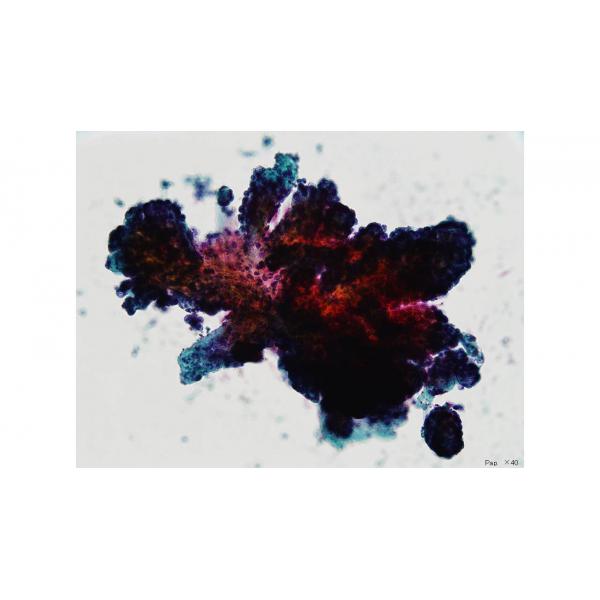

第31回日本臨床細胞学会九州連合会学会スライドカンファレンス症例 4

種別:乳腺

出題:県立宮崎病院 病理診断科 島尾 義也 先生

| 年齢 | 40歳代 | 性別 | 女性 |

| 採取部位 | 乳腺 | 採取方法 | 穿刺吸引 |

臨床所見

既往歴:

なし

現病歴:

検診にて、左乳腺外側下方に腫瘤を触知され、超音波診断にて境界明瞭粗造、後方エコーやや減弱する低エコー腫瘤を認めたため、当院外科を紹介受診された。

画像上、悪性を否定できず穿刺吸引細胞診を行った。

| 正解 | 4.Collagenous spherulosisを伴う乳管上皮増殖性病変 |

▼選択肢及び投票結果

| 1.腺様嚢胞癌 | 40件 | (29.0%) | |

|---|---|---|---|

| 2.非浸潤性乳管癌 | 2件 | (1.4%) | |

| 3.乳頭腺管癌 | 1件 | (0.7%) | |

| 4.Collagenous spherulosisを伴う乳管上皮増殖性病変 | 85件 | (61.6%) | |

| 5.基質産生癌 | 10件 | (7.2%) | |

| 投票総数 | 138件 | (100%) |